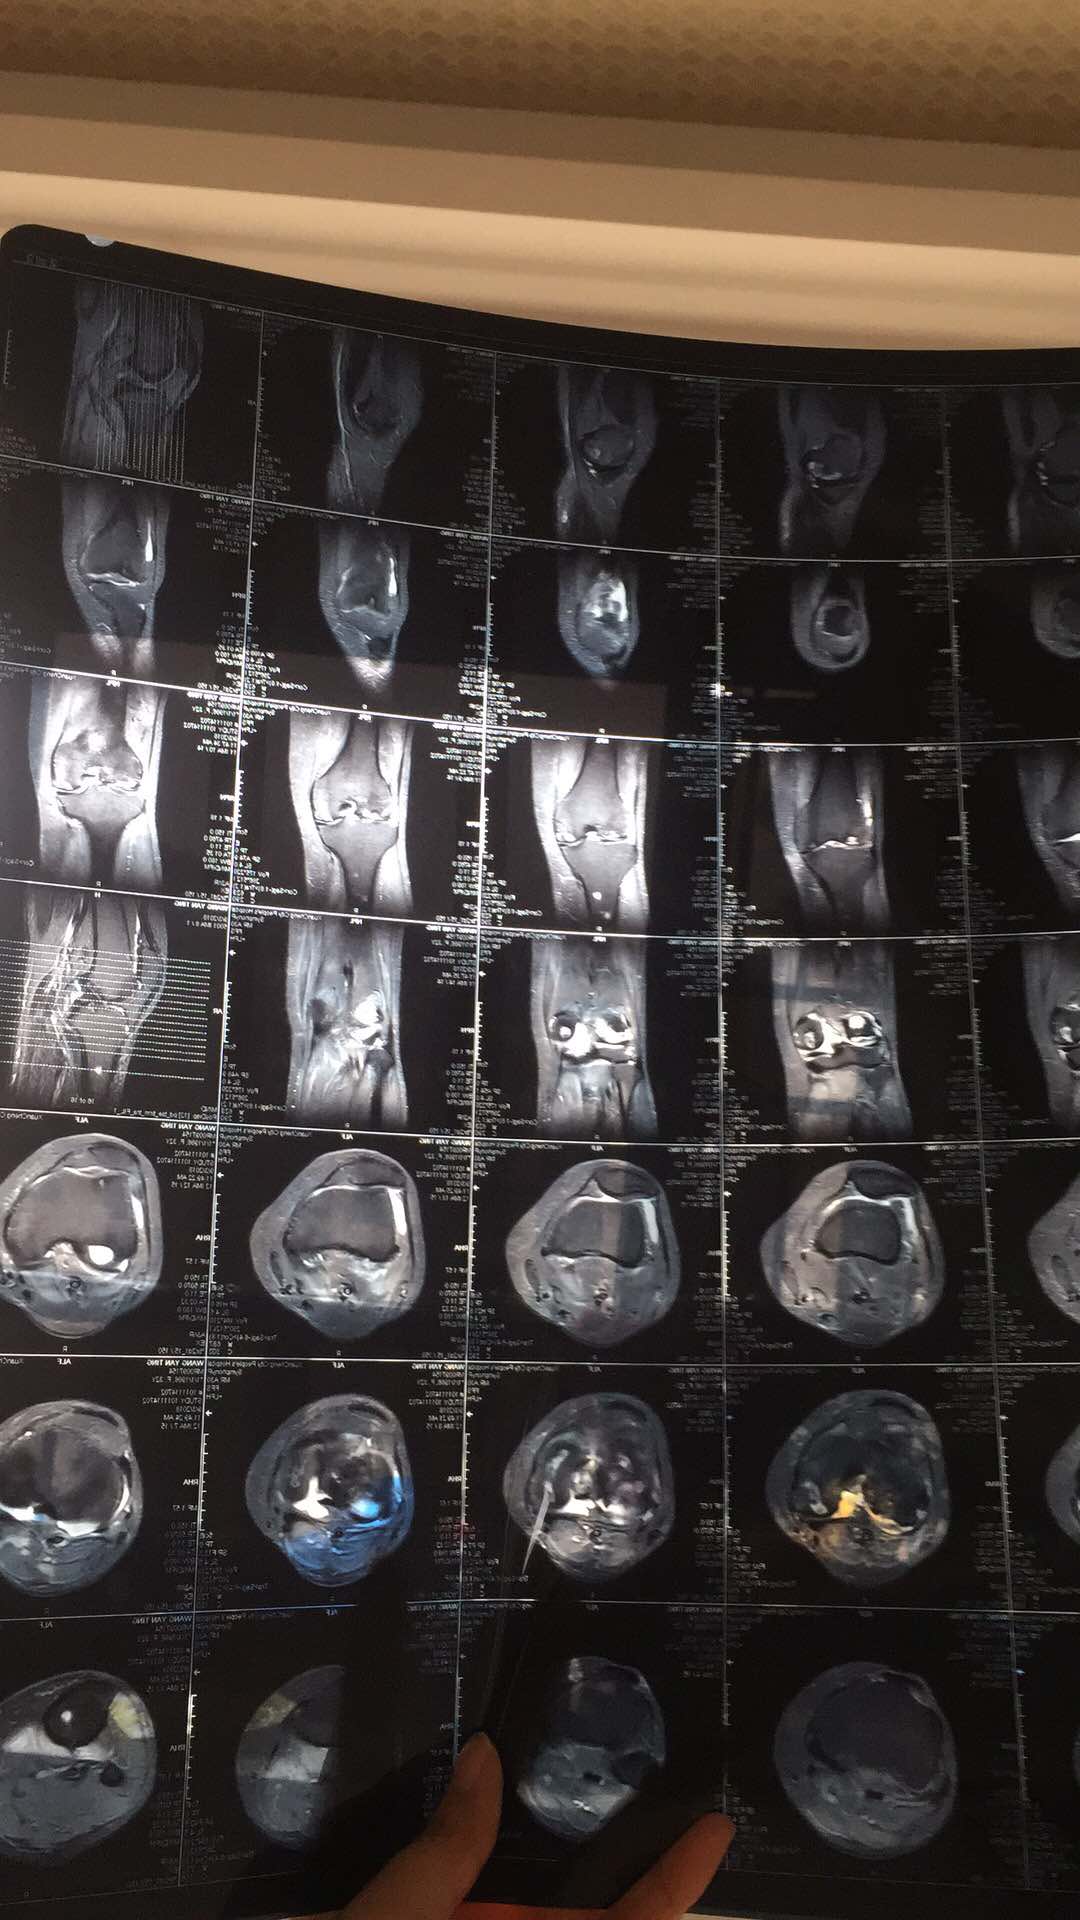

坏死的膝盖